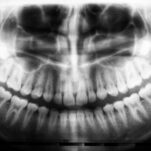

No matter the cause of facial trauma, a thorough physical examination is essential. X-rays, scans, or other imaging may be used to assess the intricate structure of bones and soft tissues in your face.